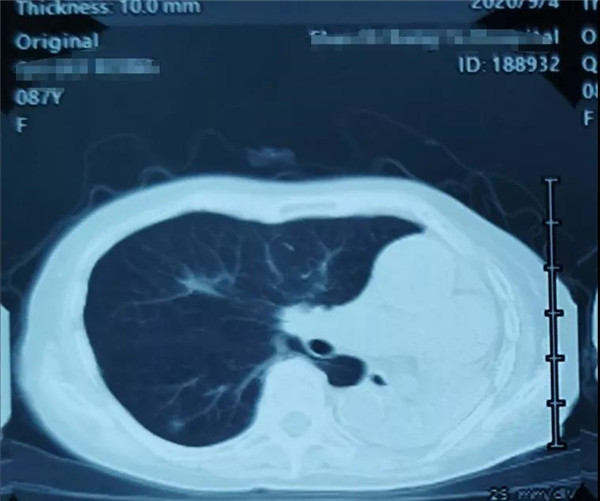

曲奶奶入院后进行了全面的身体评估,检查结果如前面所述,不容乐观(图2)。尹主任充分了解患者身体情况后,决定目前的首要任务是纠正老人脆弱的身体状况。在尹主任的安排下,先后请医院相关科室会诊,对曲奶奶目前合并的多种并发症进行治疗。在一附院骨科医护人员的照顾下,曲奶奶经过1周的调理,褥疮、低蛋白血症、贫血、碱中毒、电解质紊乱、心肾功能均得到了较好的改善。然而由于曲奶奶4年前左肺被诊断为“肺癌”,左肺目前已实变,仅靠右肺来维持呼吸(图3),因此手术无法进行气管插管,只能选择椎管内麻醉。

图3.曲奶奶入院前胸部CT检查,可见左肺实变伴右肺炎症